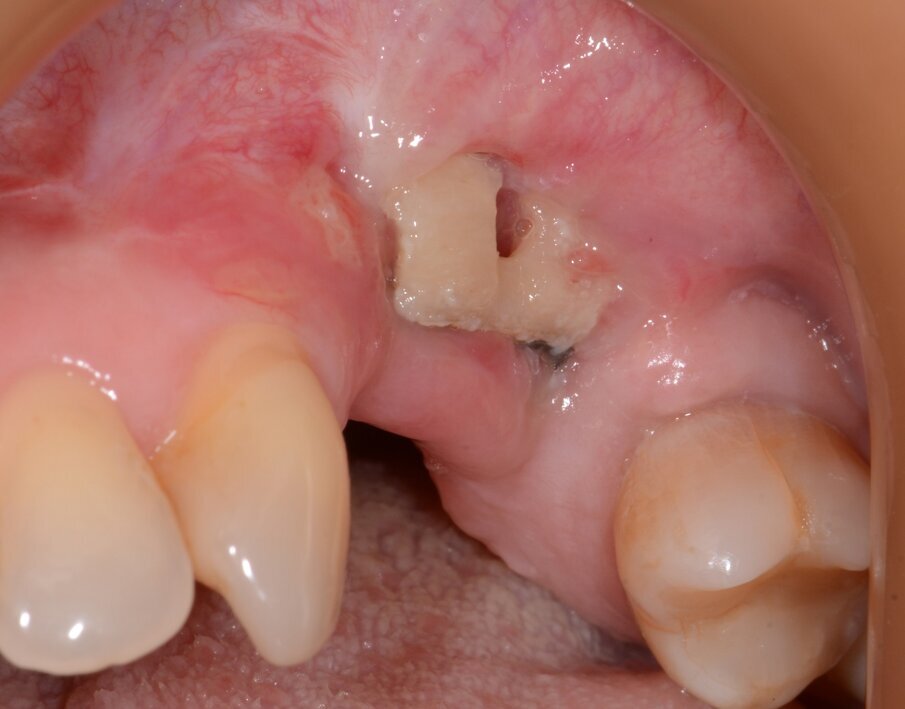

The implant apicectomy in Case 3 shows that one year after the immediate implantation with immediate loading there was inflammation around the implant apex. The rest was properly integrated (Figs. 13–20).

Fig. 16: Granulation tissue removal with Er:YAG.

Fig. 17: Implant resection.